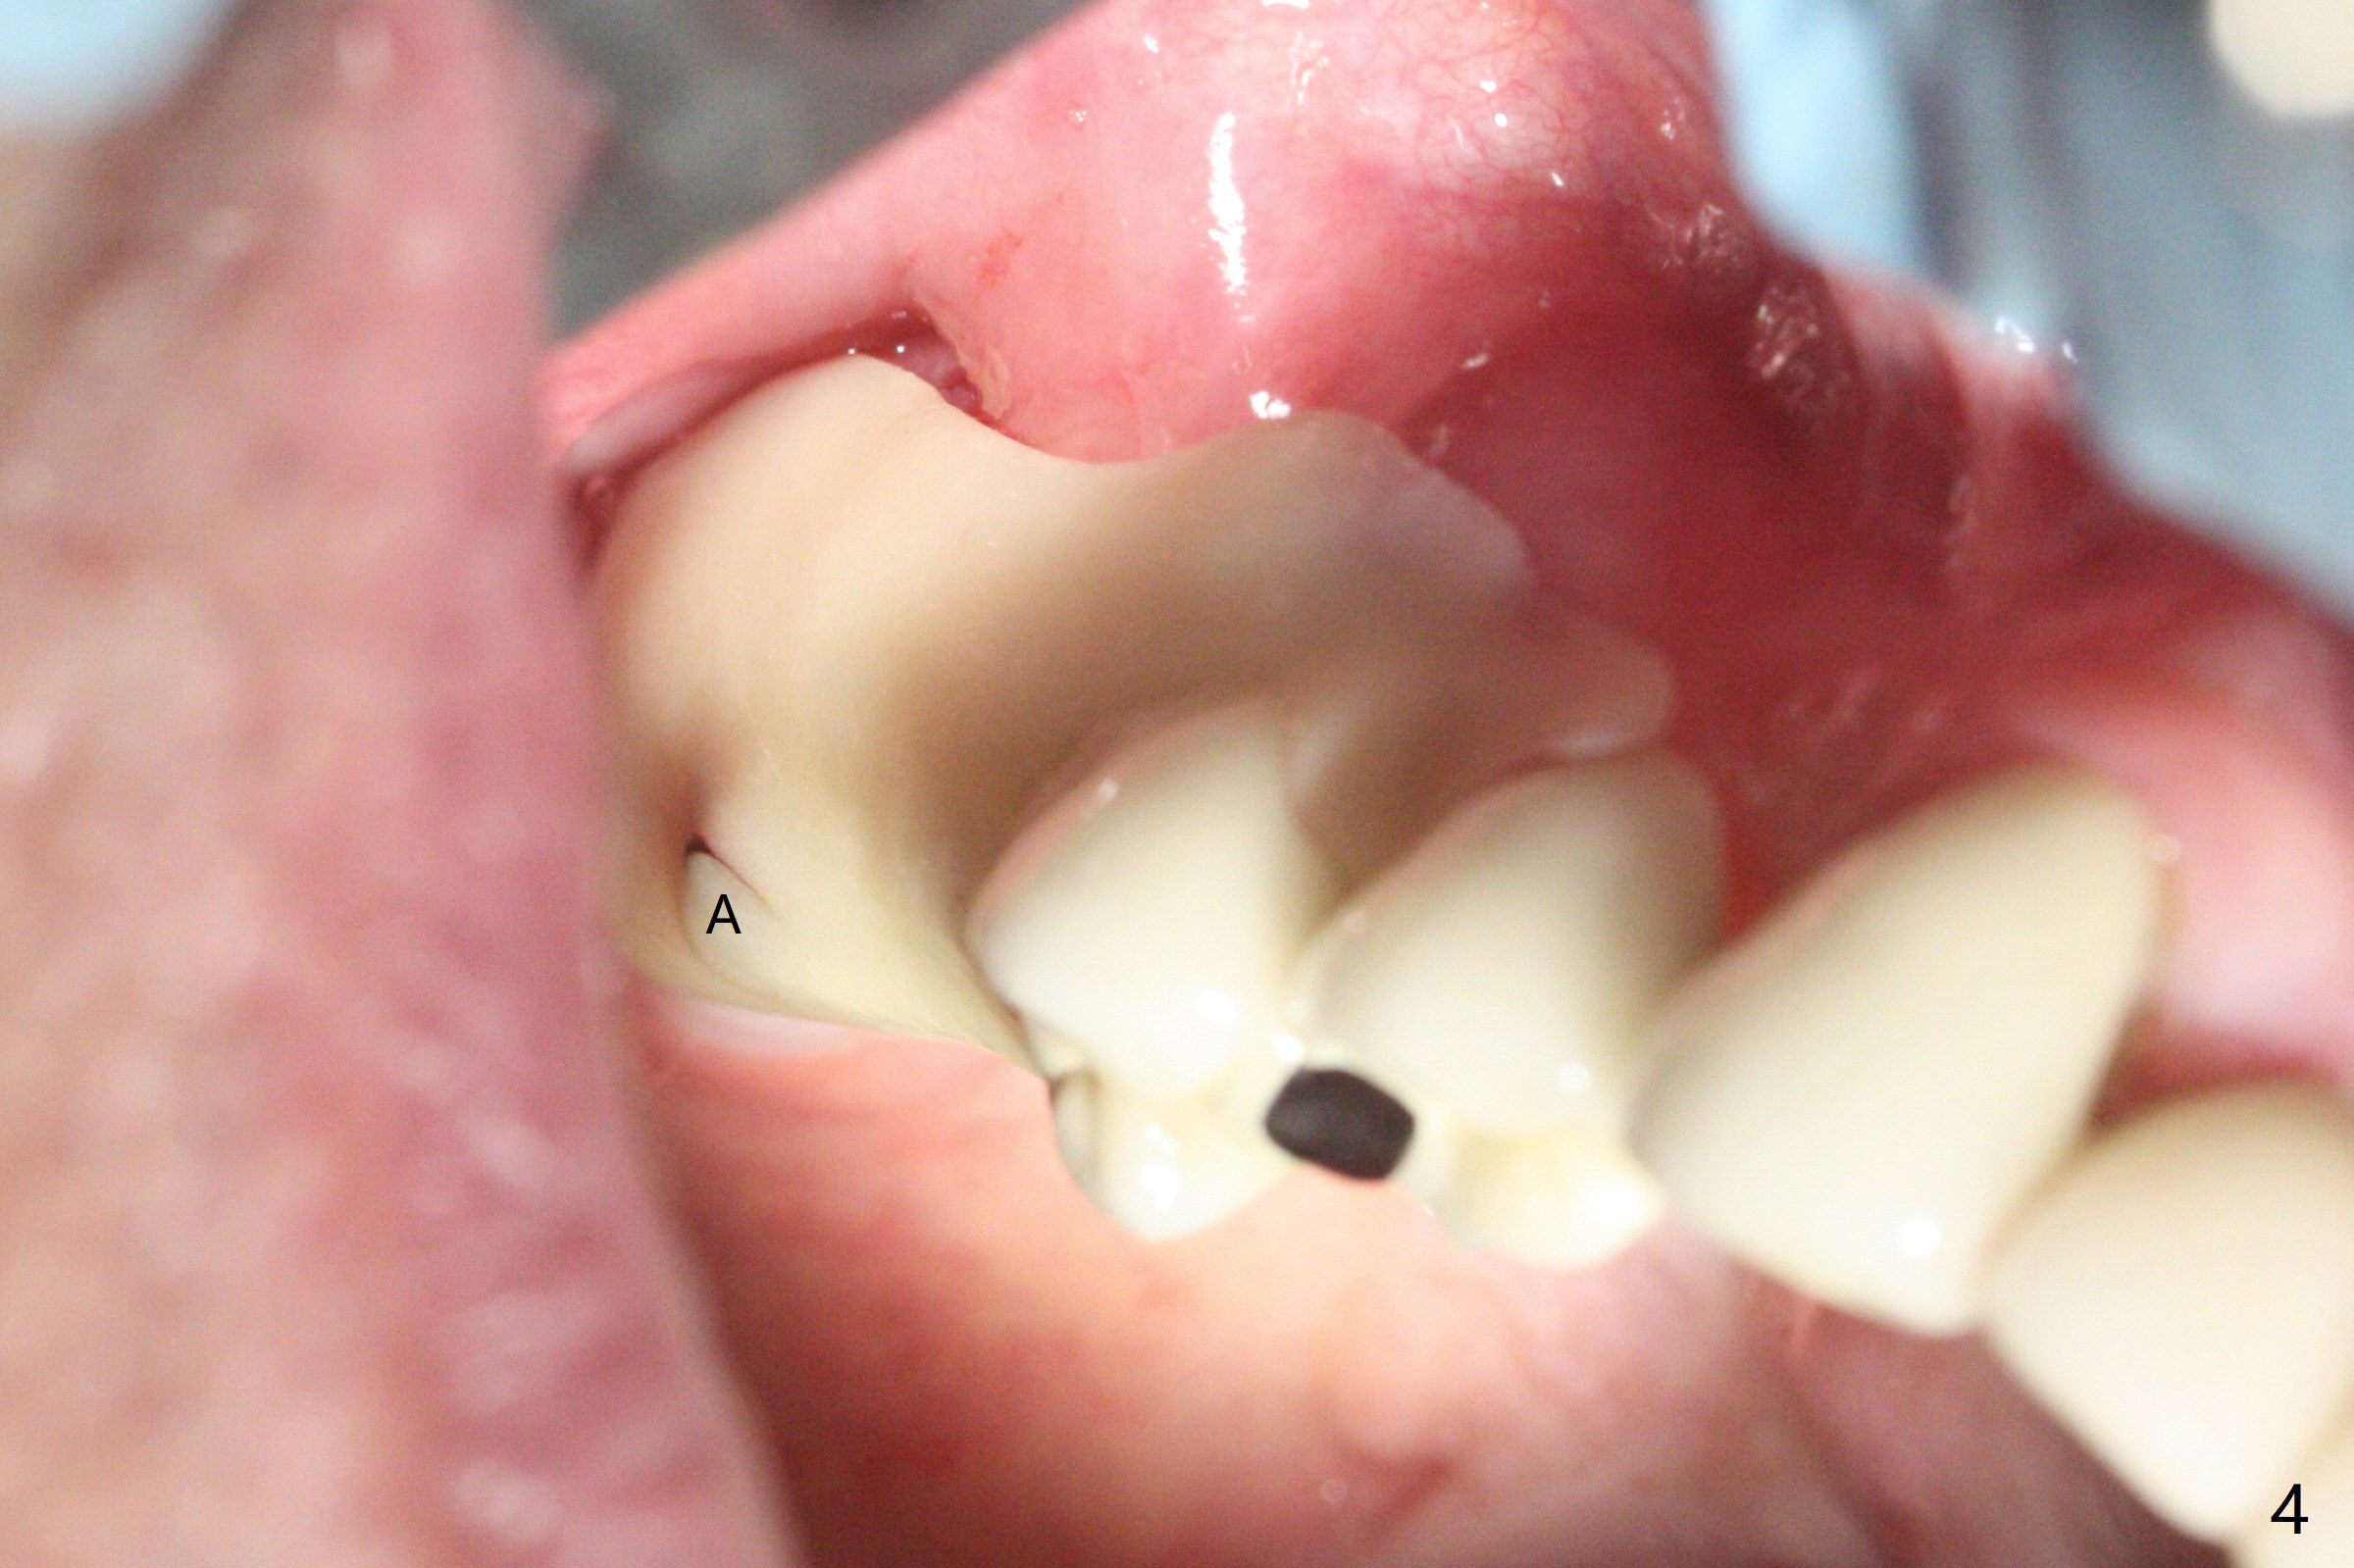

3号牙钻洞后,no-stop fixture driver好像不能完全与植体就位,所以2号牙导板钻洞和种植更不稳定(图一(咬翼片)),安置基台后(3号牙位使用5.5毫米profile drill),放置粘性骨粉(图二),2号牙植体可能穿过窦底(图三:红虚线)。由于软组织处理不好以及骨粉偏多,覆盖PRF膜后,使用树脂敷料保护伤口,两个基台起着稳定敷料作用(图四:A)。